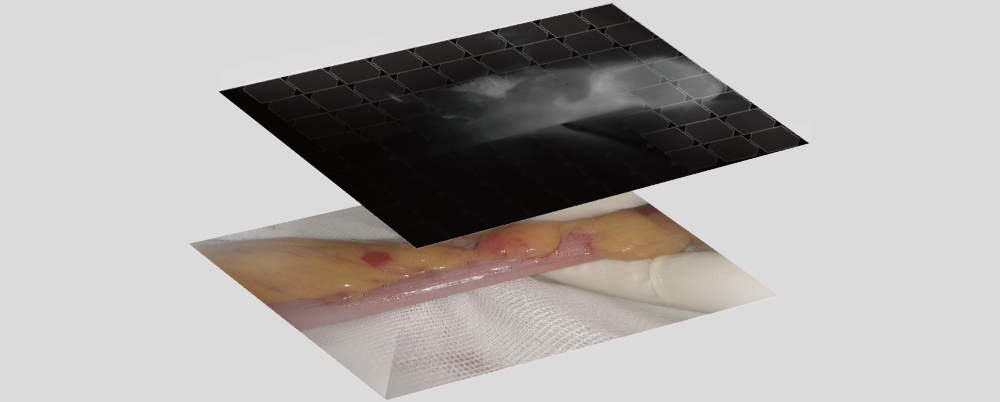

Multimodal Image Fusion

The real-time display of ultrasound images on the endoscope screen helps the surgeon localize the hidden lesion. Simultaneous recording of ultrasound and endoscope images on the same screen makes teaching and sharing more efficient.

The endoscope can display a 3D reconstruction of the organs' structure, together with the surgical view on the same screen, to assist the surgeon with real-time correction needed during the procedure.